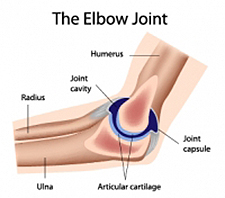

What Are Joints?

Joints are two bones joined together in a socket that allows movement. The joint is composed of bones, cartilage, tissue, muscle and fluid. The ends of the bones are covered by cartilage, which keeps the bones from rubbing together. Cartilage acts like a shock absorber to the bones. Tissue helps make up the inner wall of the socket and creates a seal to hold in the fluid. The fluid provides nutrients and lubrication to the inner wall and cartilage.

Joints are grouped according to motion types; gliding, hinge, ball and socket, and pivoting. Because of the sensitive location of joints, the pressure exerted on them and their continuous use, they are prone to pain and swelling.